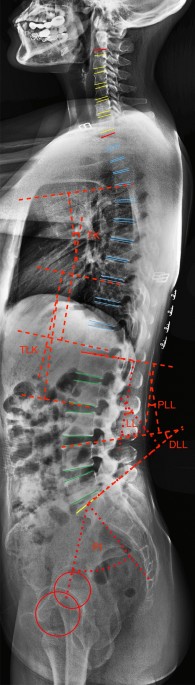

Severe Lordosis

Lordosis (Swayback): Types, Causes & Symptoms Lumbar lordosis or hyperlordosis - Back Care Clinic Lordosis: Guide To Causes, Symptoms, And Treatments What Is Lordosis? Lumbar Lordosis: Definition, Causes, Symptoms, Diagnosis, and ... Severe Lordosis